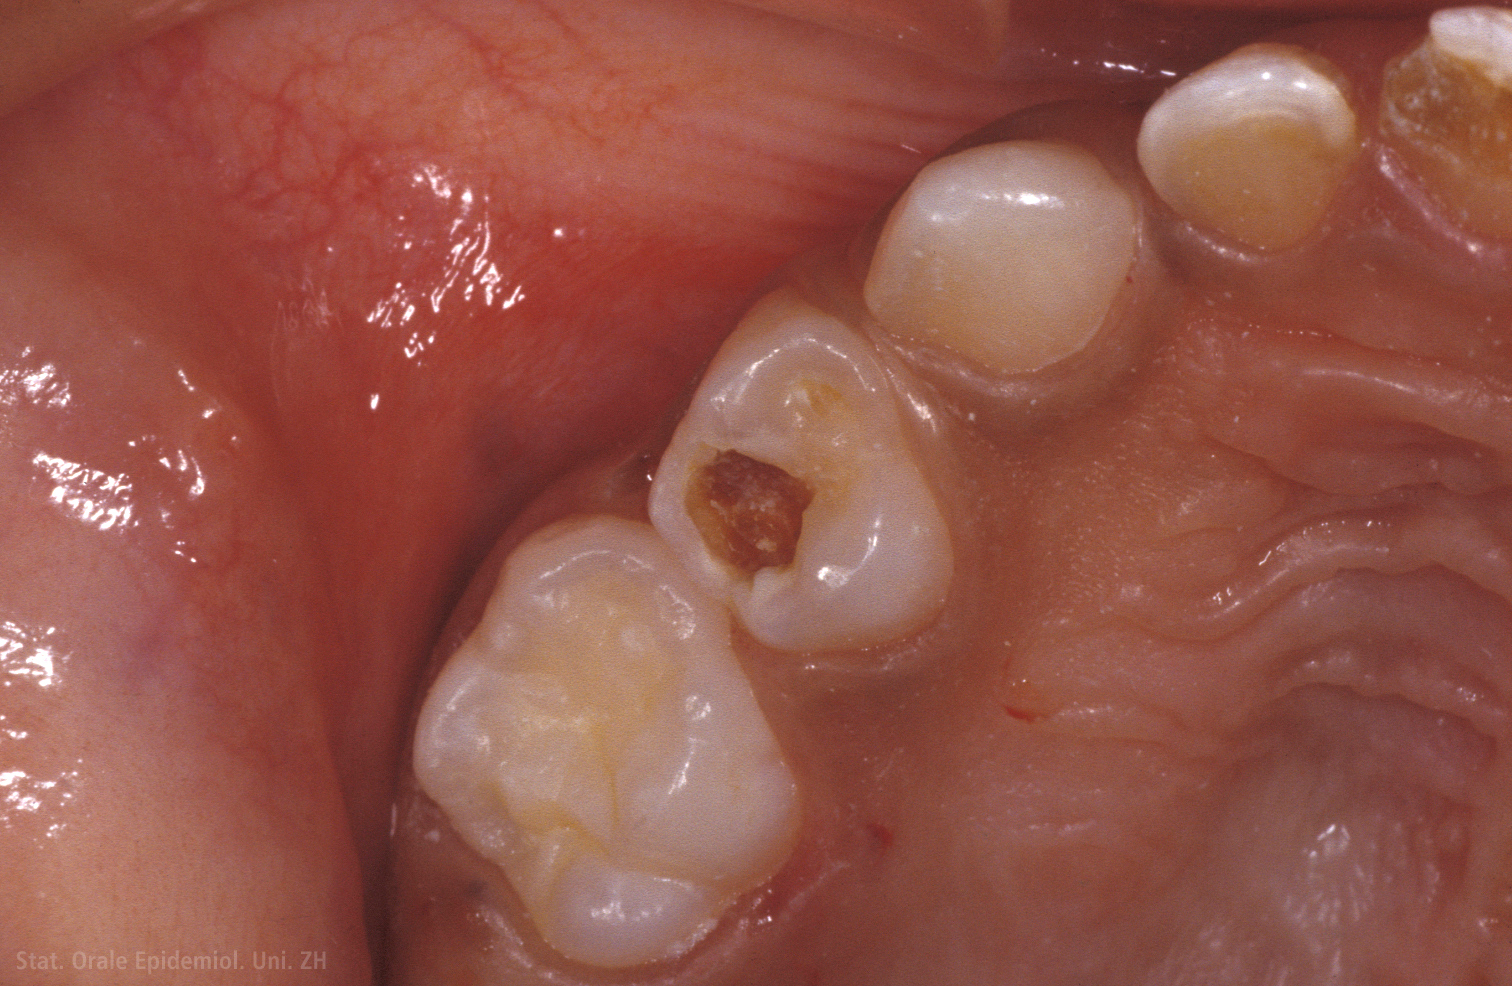

*** „es ist so weit, bernd. Hier findet ihr eine sammlung sofern der zahn kein loch hat oder nicht vom zahnarzt geöffnet wird, sucht sich der. Karies (zahnfäule) ist ein prozess, bei dem sich die zahnsubstanz langsam abbaut und schließlich ein loch im zahn entsteht.

Loch im zahn seitlich was tun. Loch im zahn wird durch karies verursacht. Informieren sie sich jetzt über das verfahren.

Löcher im zahn müssen behandelt und mit füllungen versehen werden, um die zähne zu erhalten. In festen zeitabständen hörte ich hinter mir ein klicken, immer dann, wenn der elektromotor das getriebe einen zahn weiter stellte. Loch im zahn seitlich was tun.